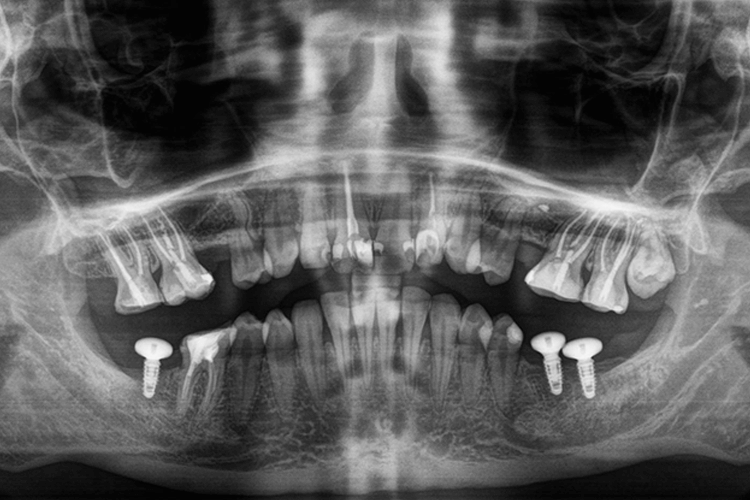

До нас в клініку звернулась пацієнтка з наступною проблемою: вторинна адентія, відсутність 5 зубів. Задача полягала не тільки у відновленні функціональності зубів, а й в покращенні усмішки в цілому.

Для відновлення відсутніх зубів нижньої щелепи запропонували встановити зубні імпланти (3 одиниці), після чого провести їх протезування керамічними коронками, а відсутні зуби верхньої щелепи відновити за допомогою мостоподібних конструкцій з опорою на сусідні зуби. Узгодили план лікування, але в процесі після установки зубних імплантів, пацієнтка звернулась до лікаря з проханням встановити зубні вініри. Нижче ми розповімо про всі етапи лікування.